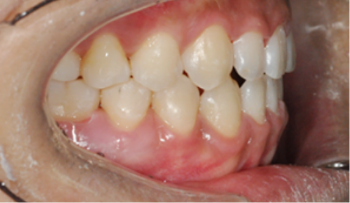

​​​​​​​Case 01. 덧니 & 치열 불규칙

덧니가 있거나 치열이 불규칙한 경우, 심미적으로도 보기에 좋지 않지만, 기능적으로도 본연의 역할을 상실하게 됩니다.

이 경우 교정 치료 방법은 크게 치아를 빼고 하는 방법과 치아를 빼지 않고 교정하는 방법으로 나뉩니다.

교정 치료 Before & After

• 덧니 & 치열 불규칙 교정 치료 전

Before

• 덧니 & 치열 불규칙 교정 치료 후

After